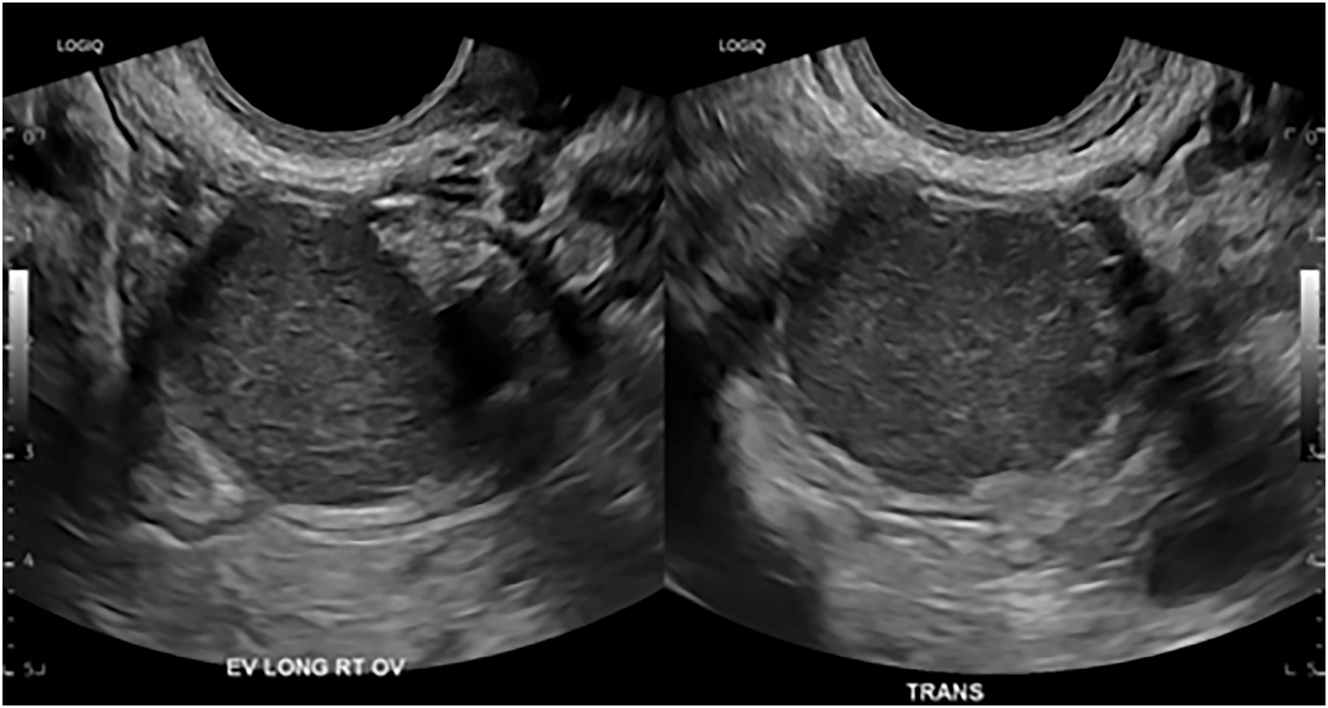

Imaging does not replace histological diagnosis, but it can raise suspicion for endometriosis and assist in patient counseling regarding treatment options. If surgery is considered, knowledge of the presence and location of DIE can assist in the preoperative planning and consideration of a multidisciplinary approach. The first-line imaging modality for patients with symptoms suspicious for endometriosis is transvaginal/transabdominal ultrasound because it is readily available and cost-effective. Figure 2 shows an ovarian endometrioma with its typical characteristic unilocular mass with ground glass echogenicity. A retrospective study showed that individuals presenting with an ovarian endometrioma had a stronger association with the presence of DIE lesions (98.2 vs. 86.2 %, p=0.01) and intestinal DIE (57.1 vs. 37.9 %, p=0.01) compared to those without ovarian endometrioma [13].

Figure 2:

A transvaginal ultrasound image of an ovarian endometrioma measuring 3.2 cm.